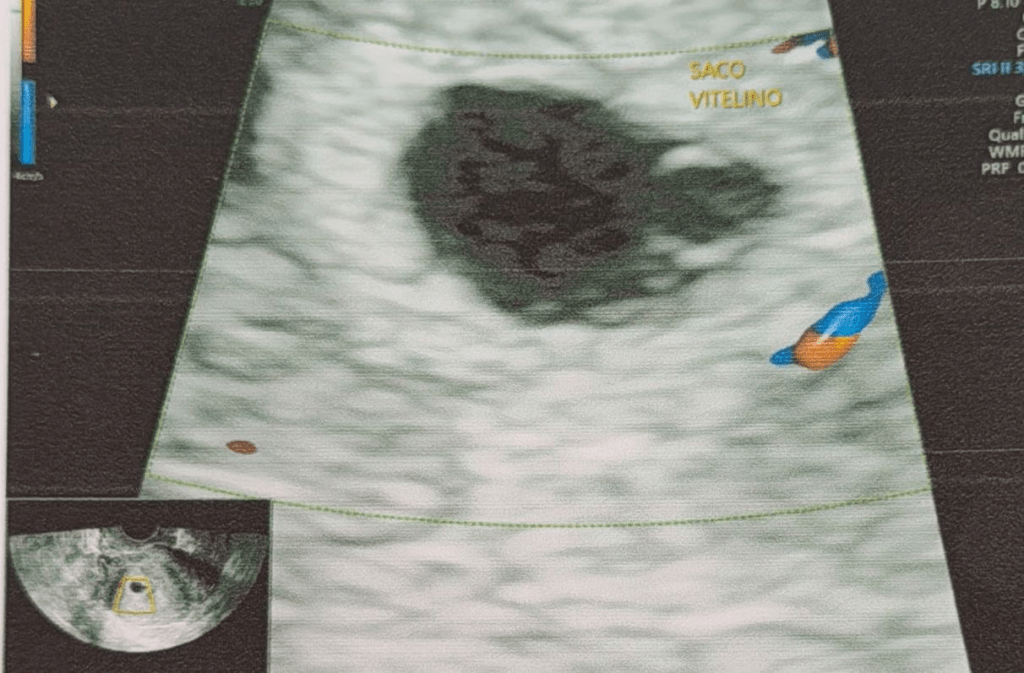

Durante el ultrasonido, la ginecóloga le informó que el saco gestacional estaba vacío. En las semanas siguientes, debería haberse visto el embrión y escucharse los latidos del corazón del bebé, pero esto no ocurrió. La doctora le explicó que, en dos semanas, su cuerpo expulsaría la bolsa al no haber embrión. Preocupada, Priscila consultó a otro especialista, quien confirmó el mismo diagnóstico.

Primera imagen donde no se refleja nada en el vientre.